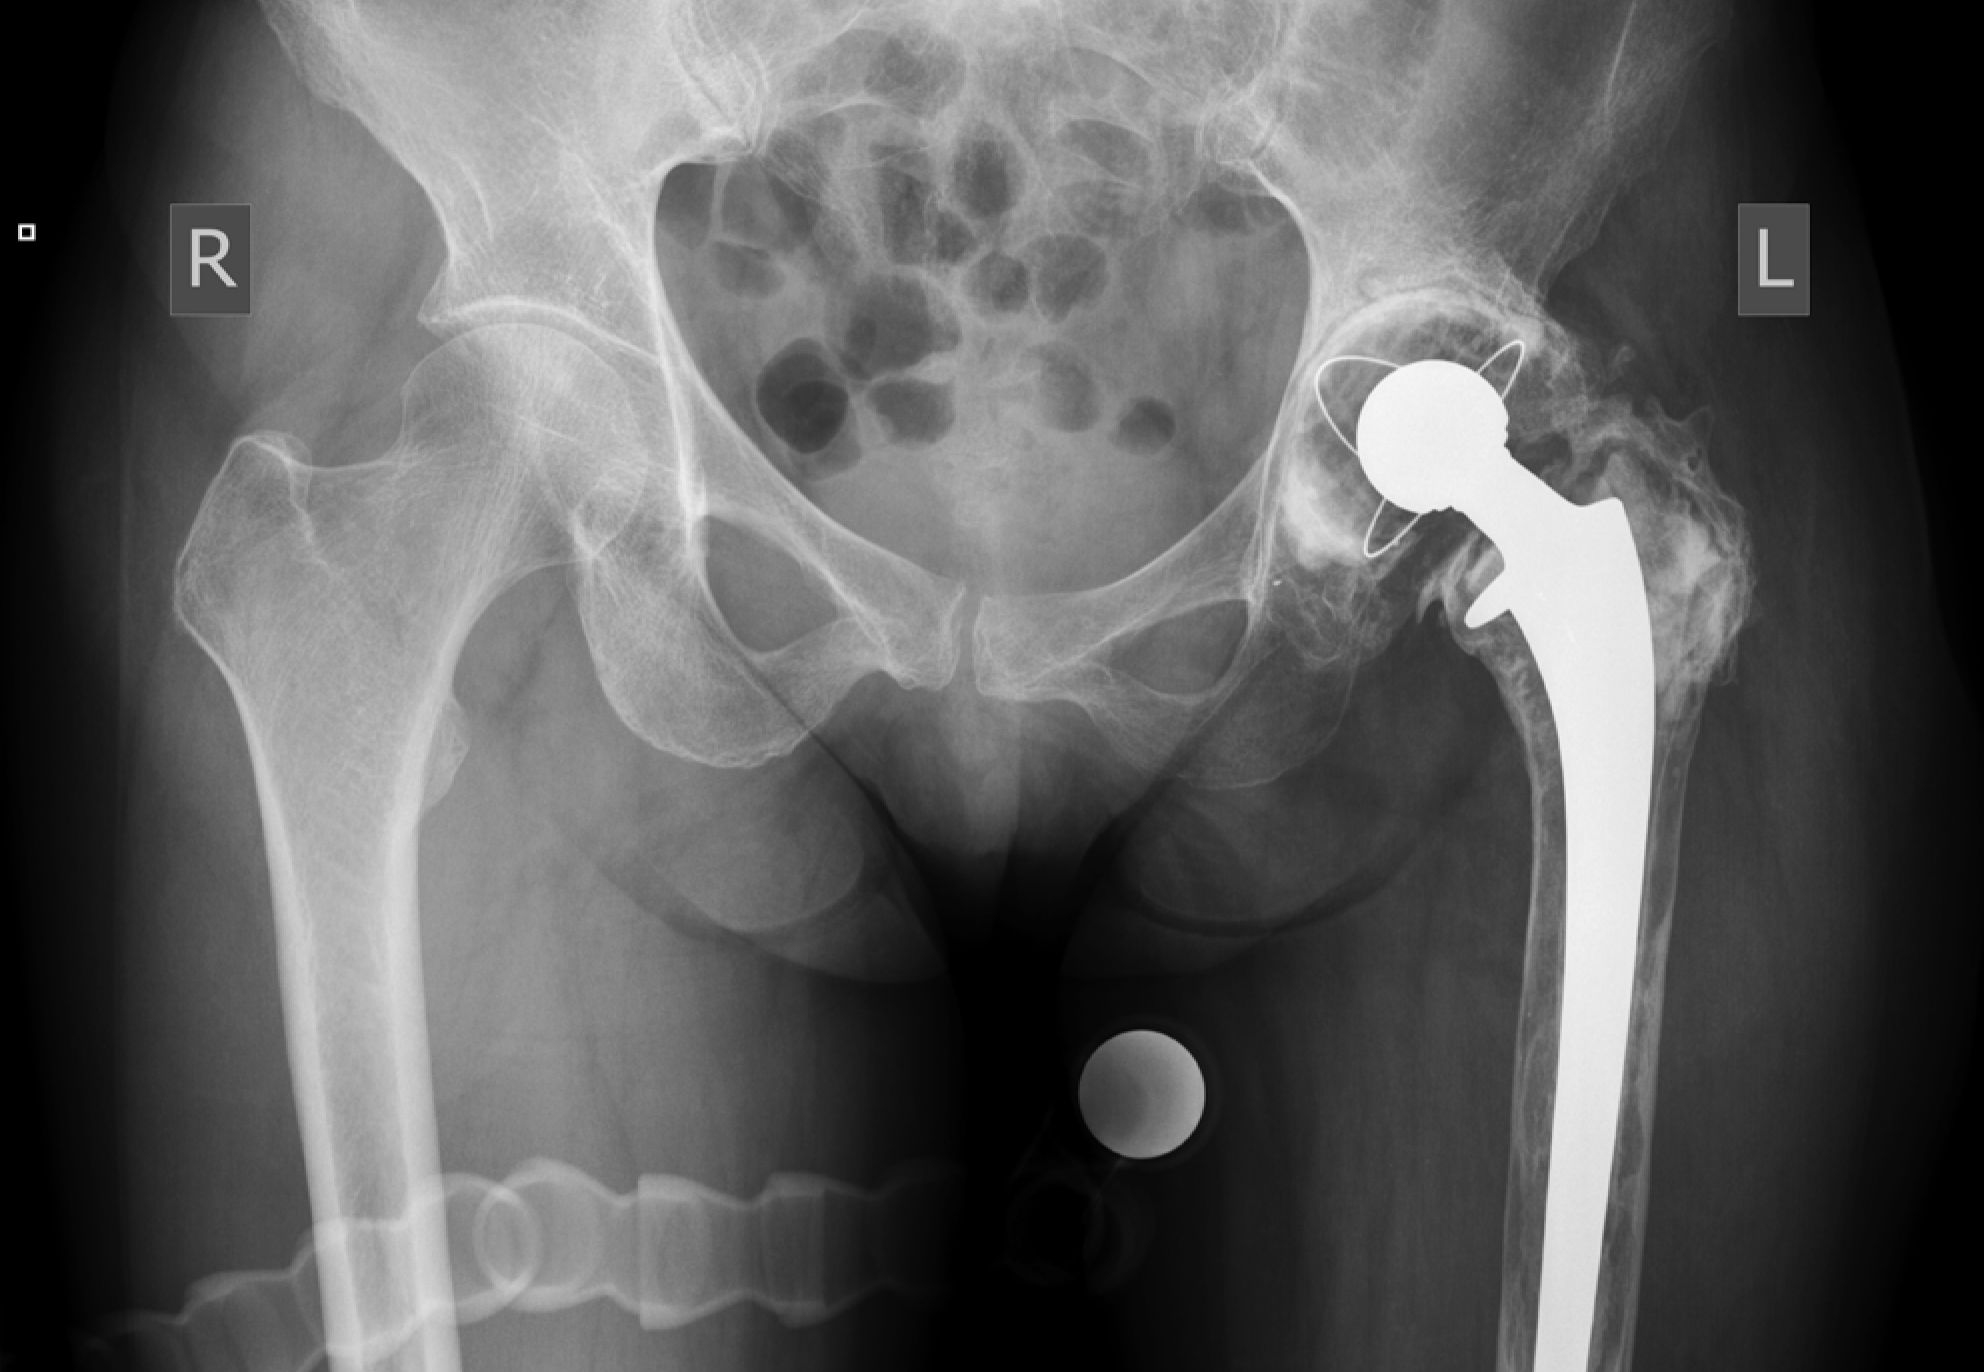

Уплотнение материала и уменьшение его объема при увеличении числа циклов нагрузки можно пояснить клиническими примерами. Проведена оценка результатов рентгенологического исследования в динамике у пациентки 59 лет (пациент 1), перенесшей двухэтапное ревизионное эндопротезирование по поводу инфицированной нестабильности компонентов эндопротеза с использованием ИКП на заключительном этапе (рис. 6). Для анализа динамики миграции тазового компонента выбраны обзорные рентгенограммы таза, полученные непосредственно после операции, через 3 года после оперативного вмешательства и на последнем контрольном осмотре через 7 лет (рис. 7). Абсолютные значения представлены в таблице 3.

Рис. 6. Обзорная рентгенограмма таза пациента 1 с признаками расшатывания тазового и бедренного компонентов эндопротеза левого ТБС, остеолизом бедренной кости слева

Figure 6. Plain X-ray of the pelvis of patient 1. Signs of loosening of the pelvic and femoral components of the left hip joint endoprosthesis and femoral osteolysis on the left are observed

Проведен анализ обзорных рентгенограмм таза пациента 53 лет (пациент 2), перенесшего ревизионное эндопротезирование левого тазобедренного сустава по поводу асептического расшатывания компонентов эндопротеза тазобедренного сустава с применением ИКП на тазовом и бедренном сегментах (рис. 8).

Рис. 8. Обзорная рентгенограмма таза пациента 2 с признаками расшатывания тазового и бедренного компонентов эндопротеза левого ТБС с остеолизом бедренной кости слева

Figure 8. Plain X-ray of the pelvis of patient 2. Signs of loosening of the pelvic and femoral components of the left hip joint endoprosthesis and femoral osteolysis on the left are observed